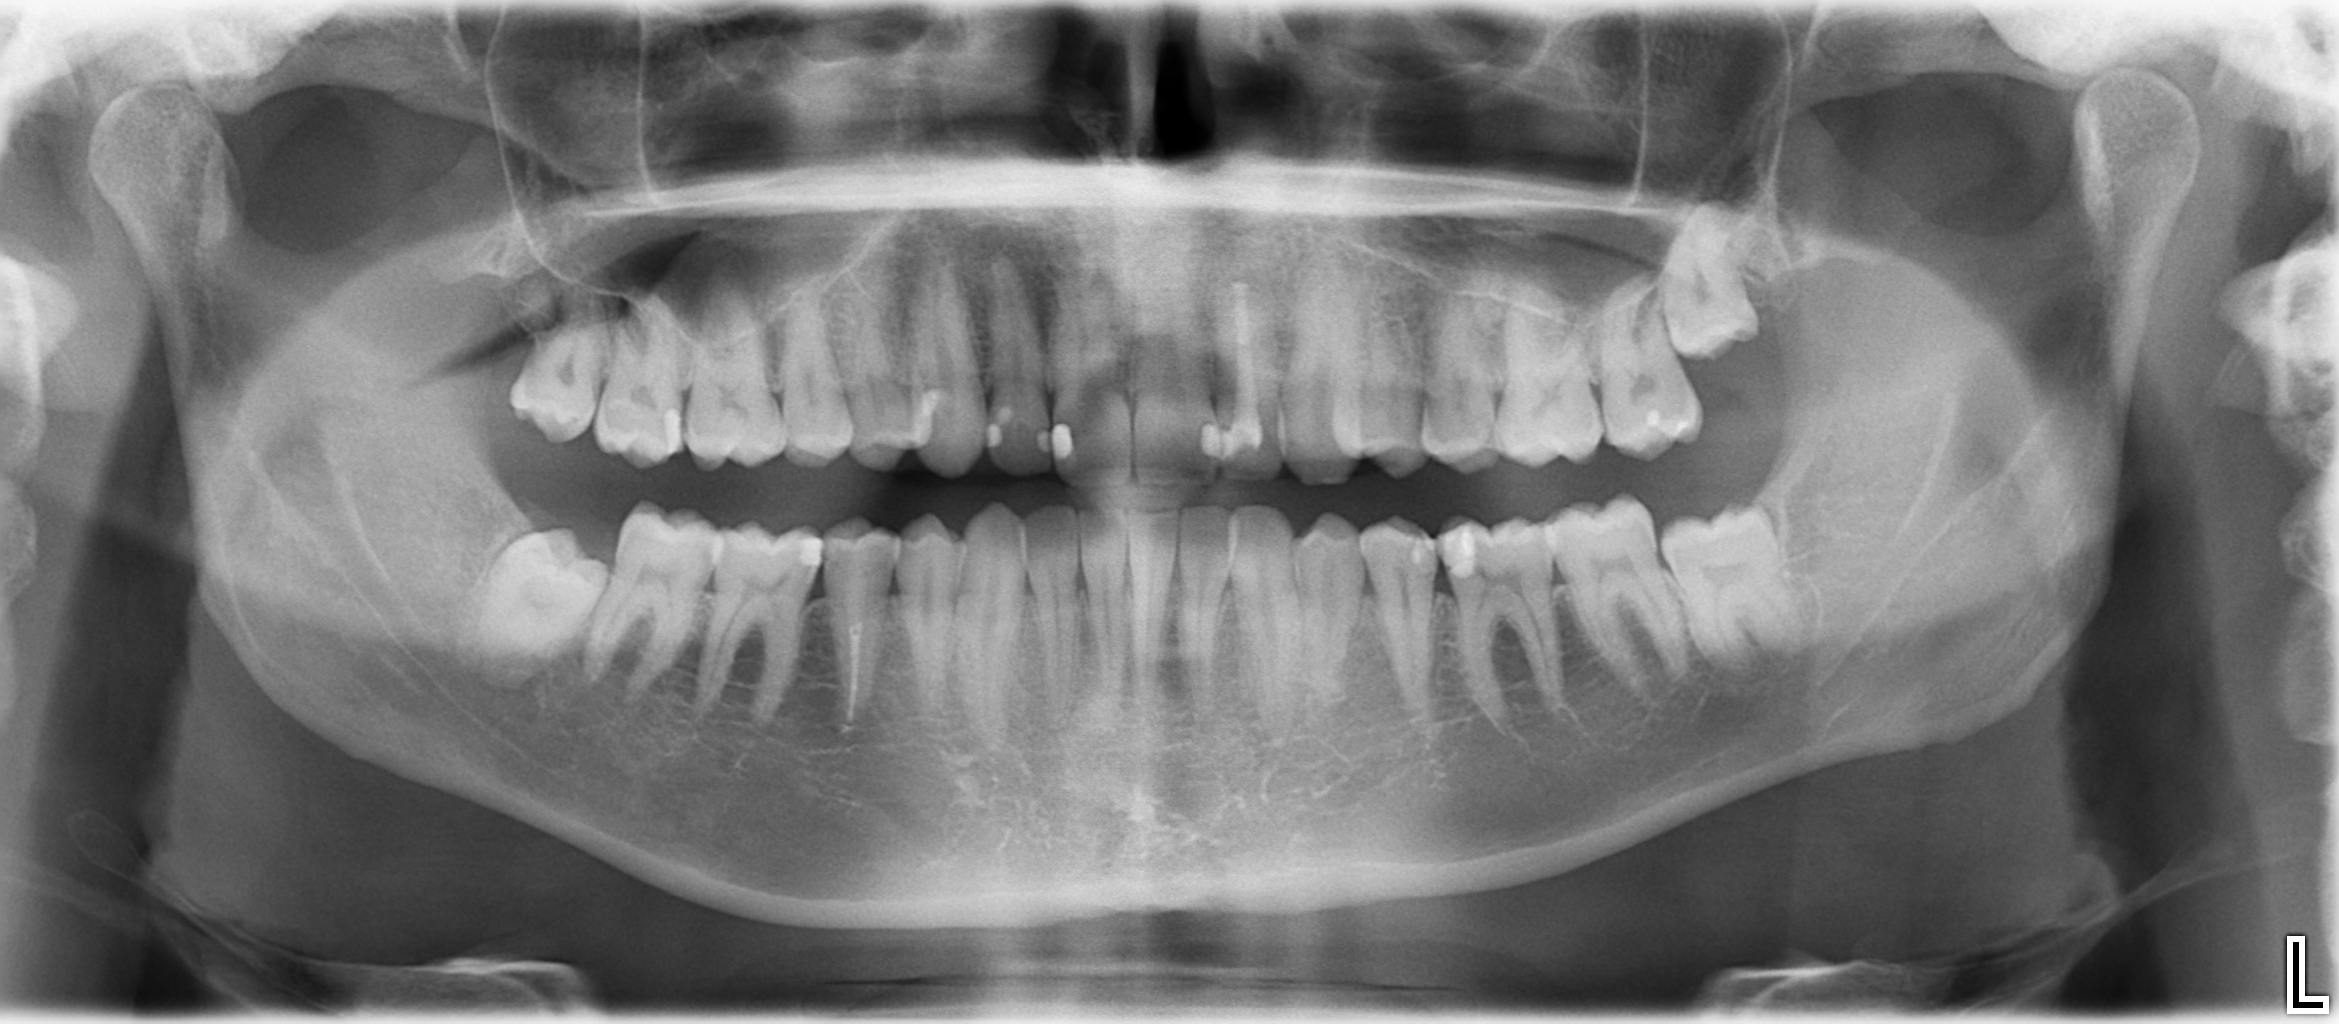

können Sie einmal das beigefügte OPTG sichten und bezüglich Zahnstatus bewerten? Gibt es hier Baustellen, welche auf jeden Fall angegangen werden sollten?

- 17, 36, 46 ala long ein keramikinlay machen

- 22, 45 gegossenen stift + krone

- bei den frontzähnen sobald die kunststofffüllungen über die zeit größer werden veneers